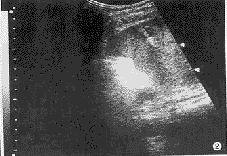

图1 治疗前超声检查示肝右叶实性肿块;

图2 图1同一病例治疗后肝右叶肿块缩小,呈条索状强回声;

例1,男性,52岁,肝癌术后3个月,发现肝内 4.0 cm×5.0 cm和 2.0 cm×3.0 cm 2个肿块,全身情况较差,食欲下降。3次微波治疗后复查肿块明显缩小,其内血流消失,活检证实肿块全部坏死,5个月后超声检查仅见小钙化点,7~8个月后经多家医院CT、B超检查未见肿块,AFP正常,患者已恢复工作,无任何不适(图1,2)。